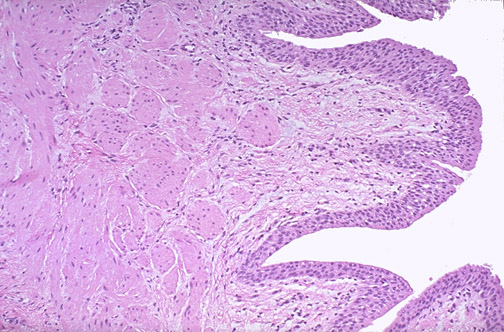

At medium power the muscular coats of the normal ureter are seen to consist of an

inner longitudinal

and an

outer circular

layer of smooth muscle. There is a

transitional epithelium

and underlying

lamina propria

.